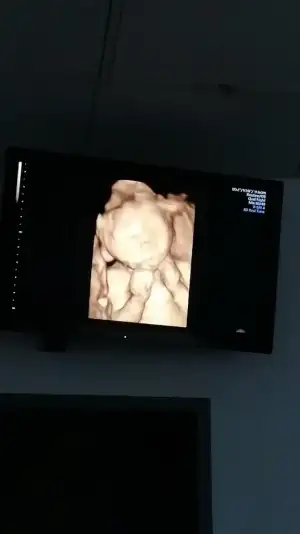

nin dediği gibi hamilelik hormonlari da duygusallastiriyor. Ikinciden umutluyum bende. Ya eşit sevsede olur

crescentee nin dediği gibi hamilelik hormonlari da duygusallastiriyor. Ikinciden umutluyum bende. Ya eşit sevsede olur